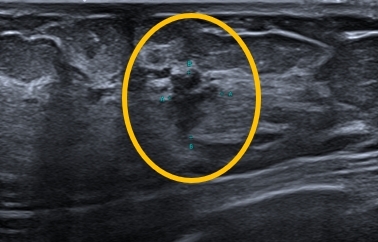

이어진 유방초음파 검사에서는 왼쪽 유두 아래 켠으로

▶ 1cm 보다 작은 크기의

▶ 경계가 불규칙하면서 뾰족뾰족한 모양의 의심스러운 혹이 확인되었습니다.